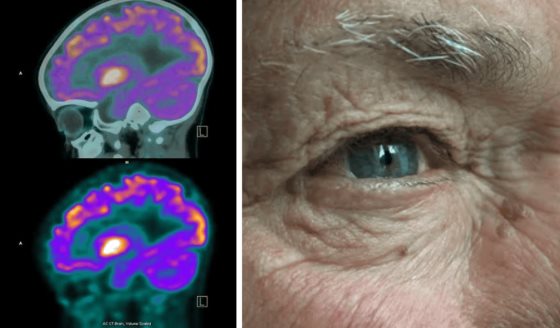

El cáncer de próstata es la segunda neoplasia maligna más diagnosticada en hombres y la tercera causa de muerte por cáncer en esta población.

Según la OMS, uno de cada 44 hombres fallecerá debido a esta enfermedad. Frente a los métodos convencionales como cirugía y quimioterapia, los cuales no siempre son efectivos y pueden causar efectos secundarios graves.